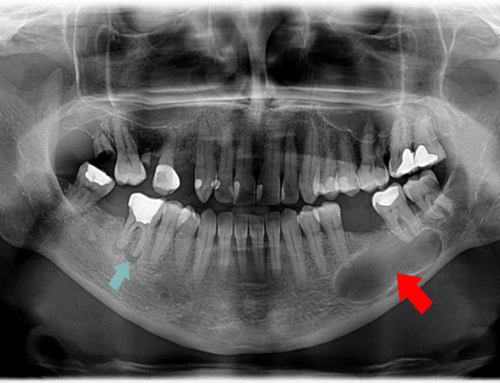

دندانهای ما بسیار قوی هستند و بهوسیله بافتهای سفت و استخوان محکم در جای خود ثابت میشوند. متأسفانه، گاهی اوقات این برای اطمینان از حفظ دائمی همه دندان ها در شرایط خاص کافی نیست. یکی از شایع ترین دلایل از دست دادن دندان ها، ضربه های تصادفی به استخوان فک است.

یک ضربه ناگهانی یا شدید می تواند به شدت به فک و لثه فرد آسیب برساند و منجر به از دست دادن چندین دندان شود. در حالی که تحت شرایط خاصی امکان بازگرداندن دندان های از دست رفته در محل خود وجود دارد، اگر ضربه بیش از حد زیاد باشد یا خود دندان ها ترک خورده یا ریشه آن ها آسیب جدی دیده باشد، درمان های جایگزین مورد نیاز است.

سایر مواردی که ممکن است منجر به از دست رفتن دندان شوند، به یکی دیگر از مسائل مربوط به سلامت دندان، مانند بیماری لثه، سرطان دهان، یا مراحل پیشرفته پوسیدگی دندان مربوط باشد.

در چنین موقعیتهایی، علاوه بر جایگزینی یا ترمیم دندانها، پرداختن به علت اصلی از دست رفتن دندانها بسیار مهم است. در شدیدترین موارد، برداشتن تمام دندانهای طبیعی بیمار ممکن است برای درمان مؤثر این بیماری ضروری باشد و نیاز به جایگزینی دندانها با مجموعه پروتزهای مصنوعی باشد.